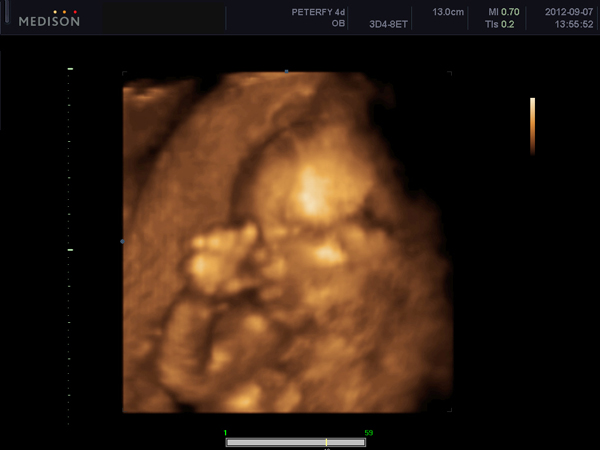

Mondjuk azt is mondta nekem a doktornő, hogy ha a laborleletek nem is igazolják, de a tünetek fennállnak, akkor is ki lehet mondani ezt a betegséget, mert lehet, hogy a határértéket nem lépi át az inzulin, de sok van, mert problémát okoz. Ellenkező esetben, hogy ha esetleg a labor kimutatja, de nem okoz tünetet, az nem tudom, hogy problémát okoz-e. Egyébként szülés után fél évvel lehet nézetni inzulint, mert terhesség alatt máshogy viselkedik a szervezet. Esetleg annyit megérhet, hogy megcsináltatod, mi meg majd jól kielemezzük, hozzáértők. De én most azt mondom, hogy ha semmilyen tüneted nincs, akkor nem biztos, hogy foglalkozni kell vele, tudomásul kell venni, hogy hajlamod van rá és egy kicsit tudatosabban étkezni és sportolni a jövőben.